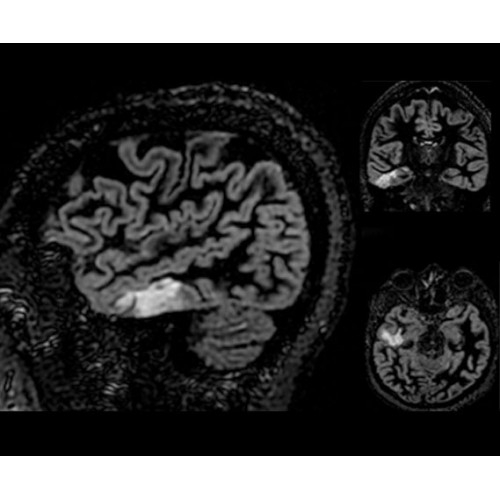

В систему SIGNA PET/MR встроены запатентованные детекторы кремниевого фотоумножителя (SiPM) и сверхчувствительные кристаллические сцинтилляторы на основе лютеция толщиной 25 мм. Благодаря этому обеспечивается исключительная чувствительность и возможность использования времяпролетной диагностики (TOF).

Кроме того, в результате использования технологии TOF и инновационной технологии реконструкции Q.Clear вы сможете добиться прекрасного соотношения сигнал/шум. А благодаря технологии нулевого времени эхо (ZTE) визуализировать костную структуру без ионизирующего излучения. Все эти разработки для улучшения качества сканирования и точности анализа помогут вам использовать весь потенциал ПЭТ/МРТ.

• TurboTOF — инновационная технология позволяет корректировать коэффициент затухания сигнала и минимизировать потери анатомических данных, создавая МР-систему для количественной визуализации.

• Q.Clear — в основу технологии легли накопленные знания о том, как минимизировать помехи при реконструкции и получить четкое изображение. При значительном улучшении качества изображения сохраняется точность расчетов. Сочетание технологии TOF и реконструкции Q.Clear — ваш надежный помощник для получения точных и достоверных данных.

• МРТ с функцией нулевого времени эхо (ZTE) отличается точностью, возможностью персональных настроек и отсутствием ионизирующего излучения. Она приходит на смену традиционному исследованию на основе рентгеновского излучения. МРТ с функцией нулевого времени эхо (ZTE) на базе SIGNA ПЭТ/МРТ является более надежной и быстрой по сравнению с системами, использующими сверхмалое время эхо (UTE).